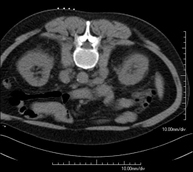

- TC Abdominopélvico

Prueba diagnóstica que consiste en obtener imágenes bi y tridimensionales del abdomen y de la pelvis de alta definición anatómica (estructuras óseas, estructuras vasculares, hígado, páncreas, vesícula biliar, riñones, glándulas suprarrenales, bazo, intestino delgado y grueso, vejiga, útero y ovarios, próstata y vesículas seminales, uréteres, etc.) mediante el empleo de un equipo de TC (Tomografía Computarizada). La mayoría de estudios requieren el empleo de contraste yodado.